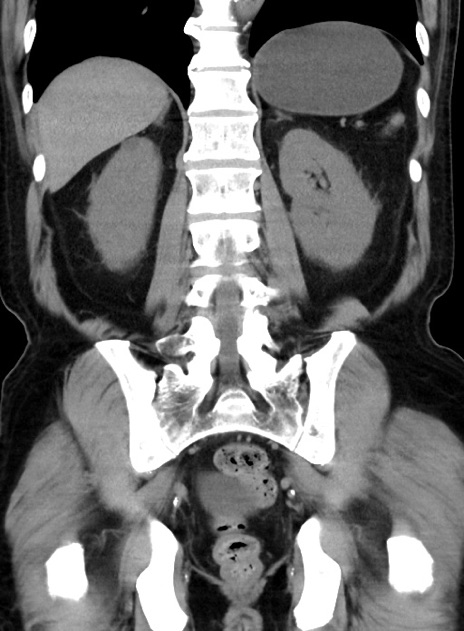

症例38(冠状断像)

【症例】70歳代 男性

【主訴】腹痛・嘔吐

【現病歴】昨晩より、嘔吐・腹痛あり。今朝になっても嘔吐あり。来院。

【既往歴】心臓バイパス手術、開腹胆摘、腸閉塞

【身体所見】BP 107/71mmHg、HR 116/min、腹部:平坦、軟、下腹部に軽度圧痛あり。反跳痛なし。

【データ】WBC 15100、CRP 0.32